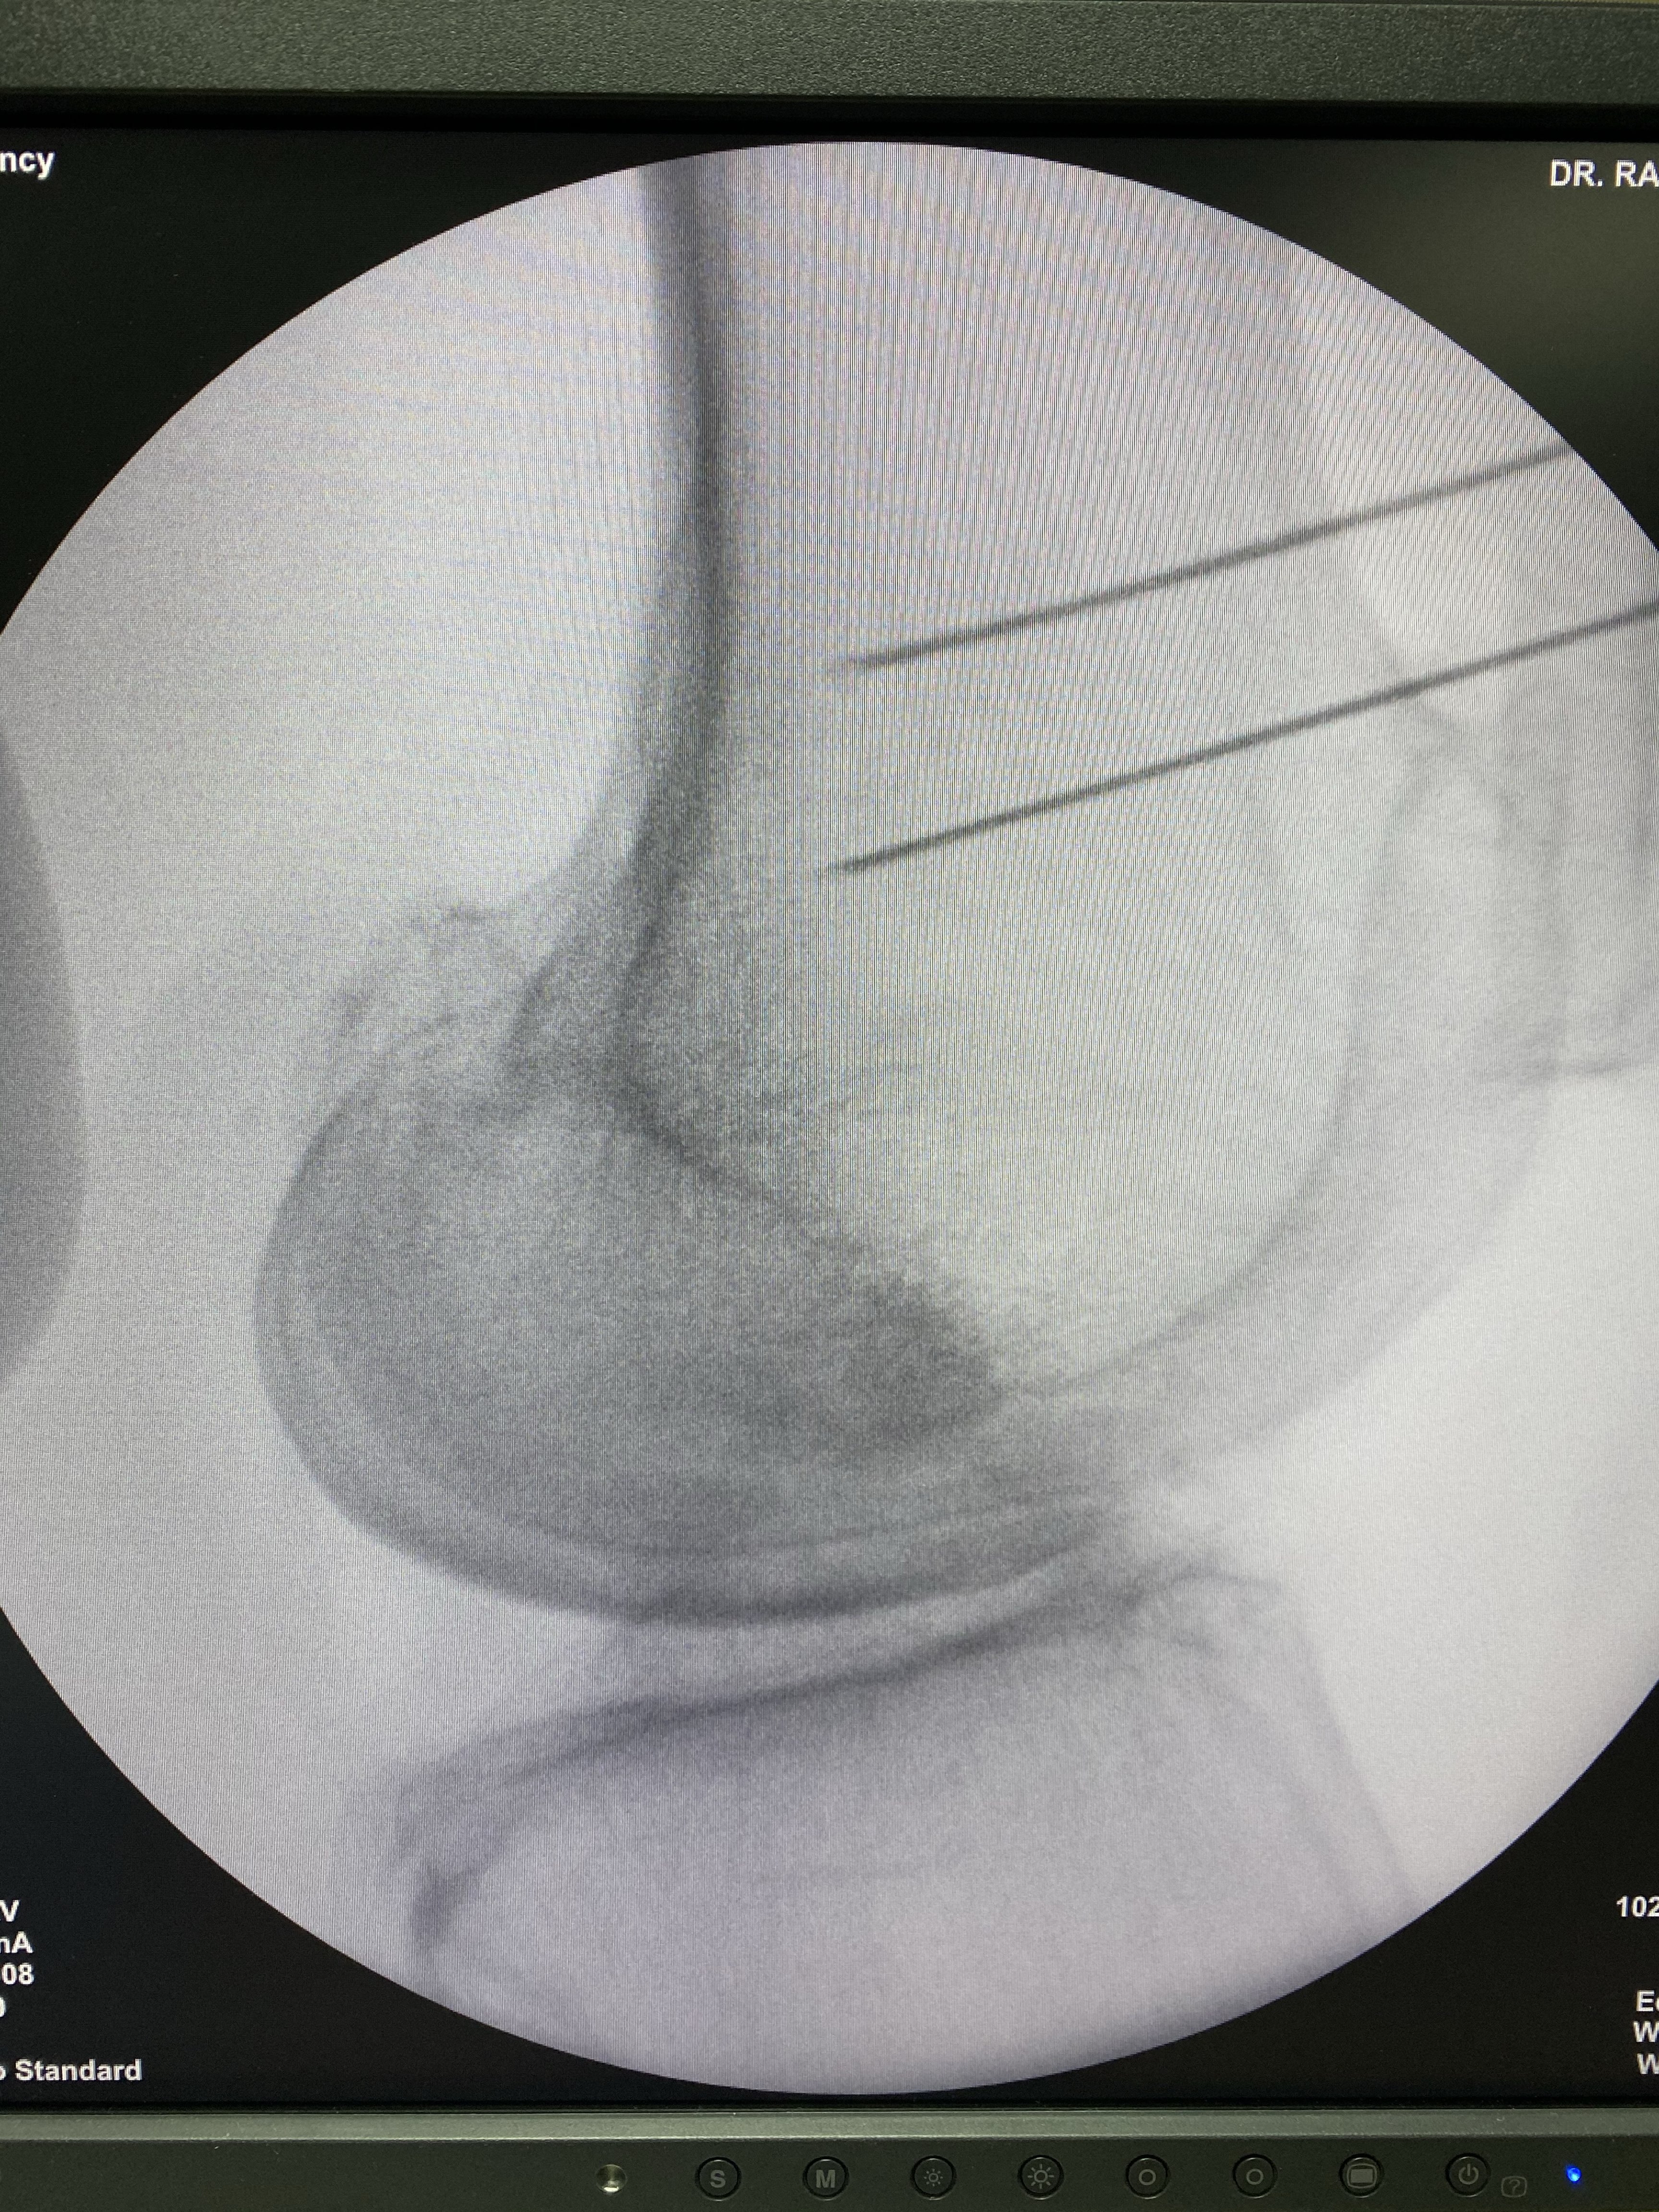

Radiofrecuencia en Articulaciones: Cadera

Indicada para pacientes con artrosis de cadera o dolor persistente luego de reemplazo articular. Se aplican pulsos de radiofrecuencia sobre los nervios sensitivos que rodean la articulación.

Radiofrecuencia de cadera